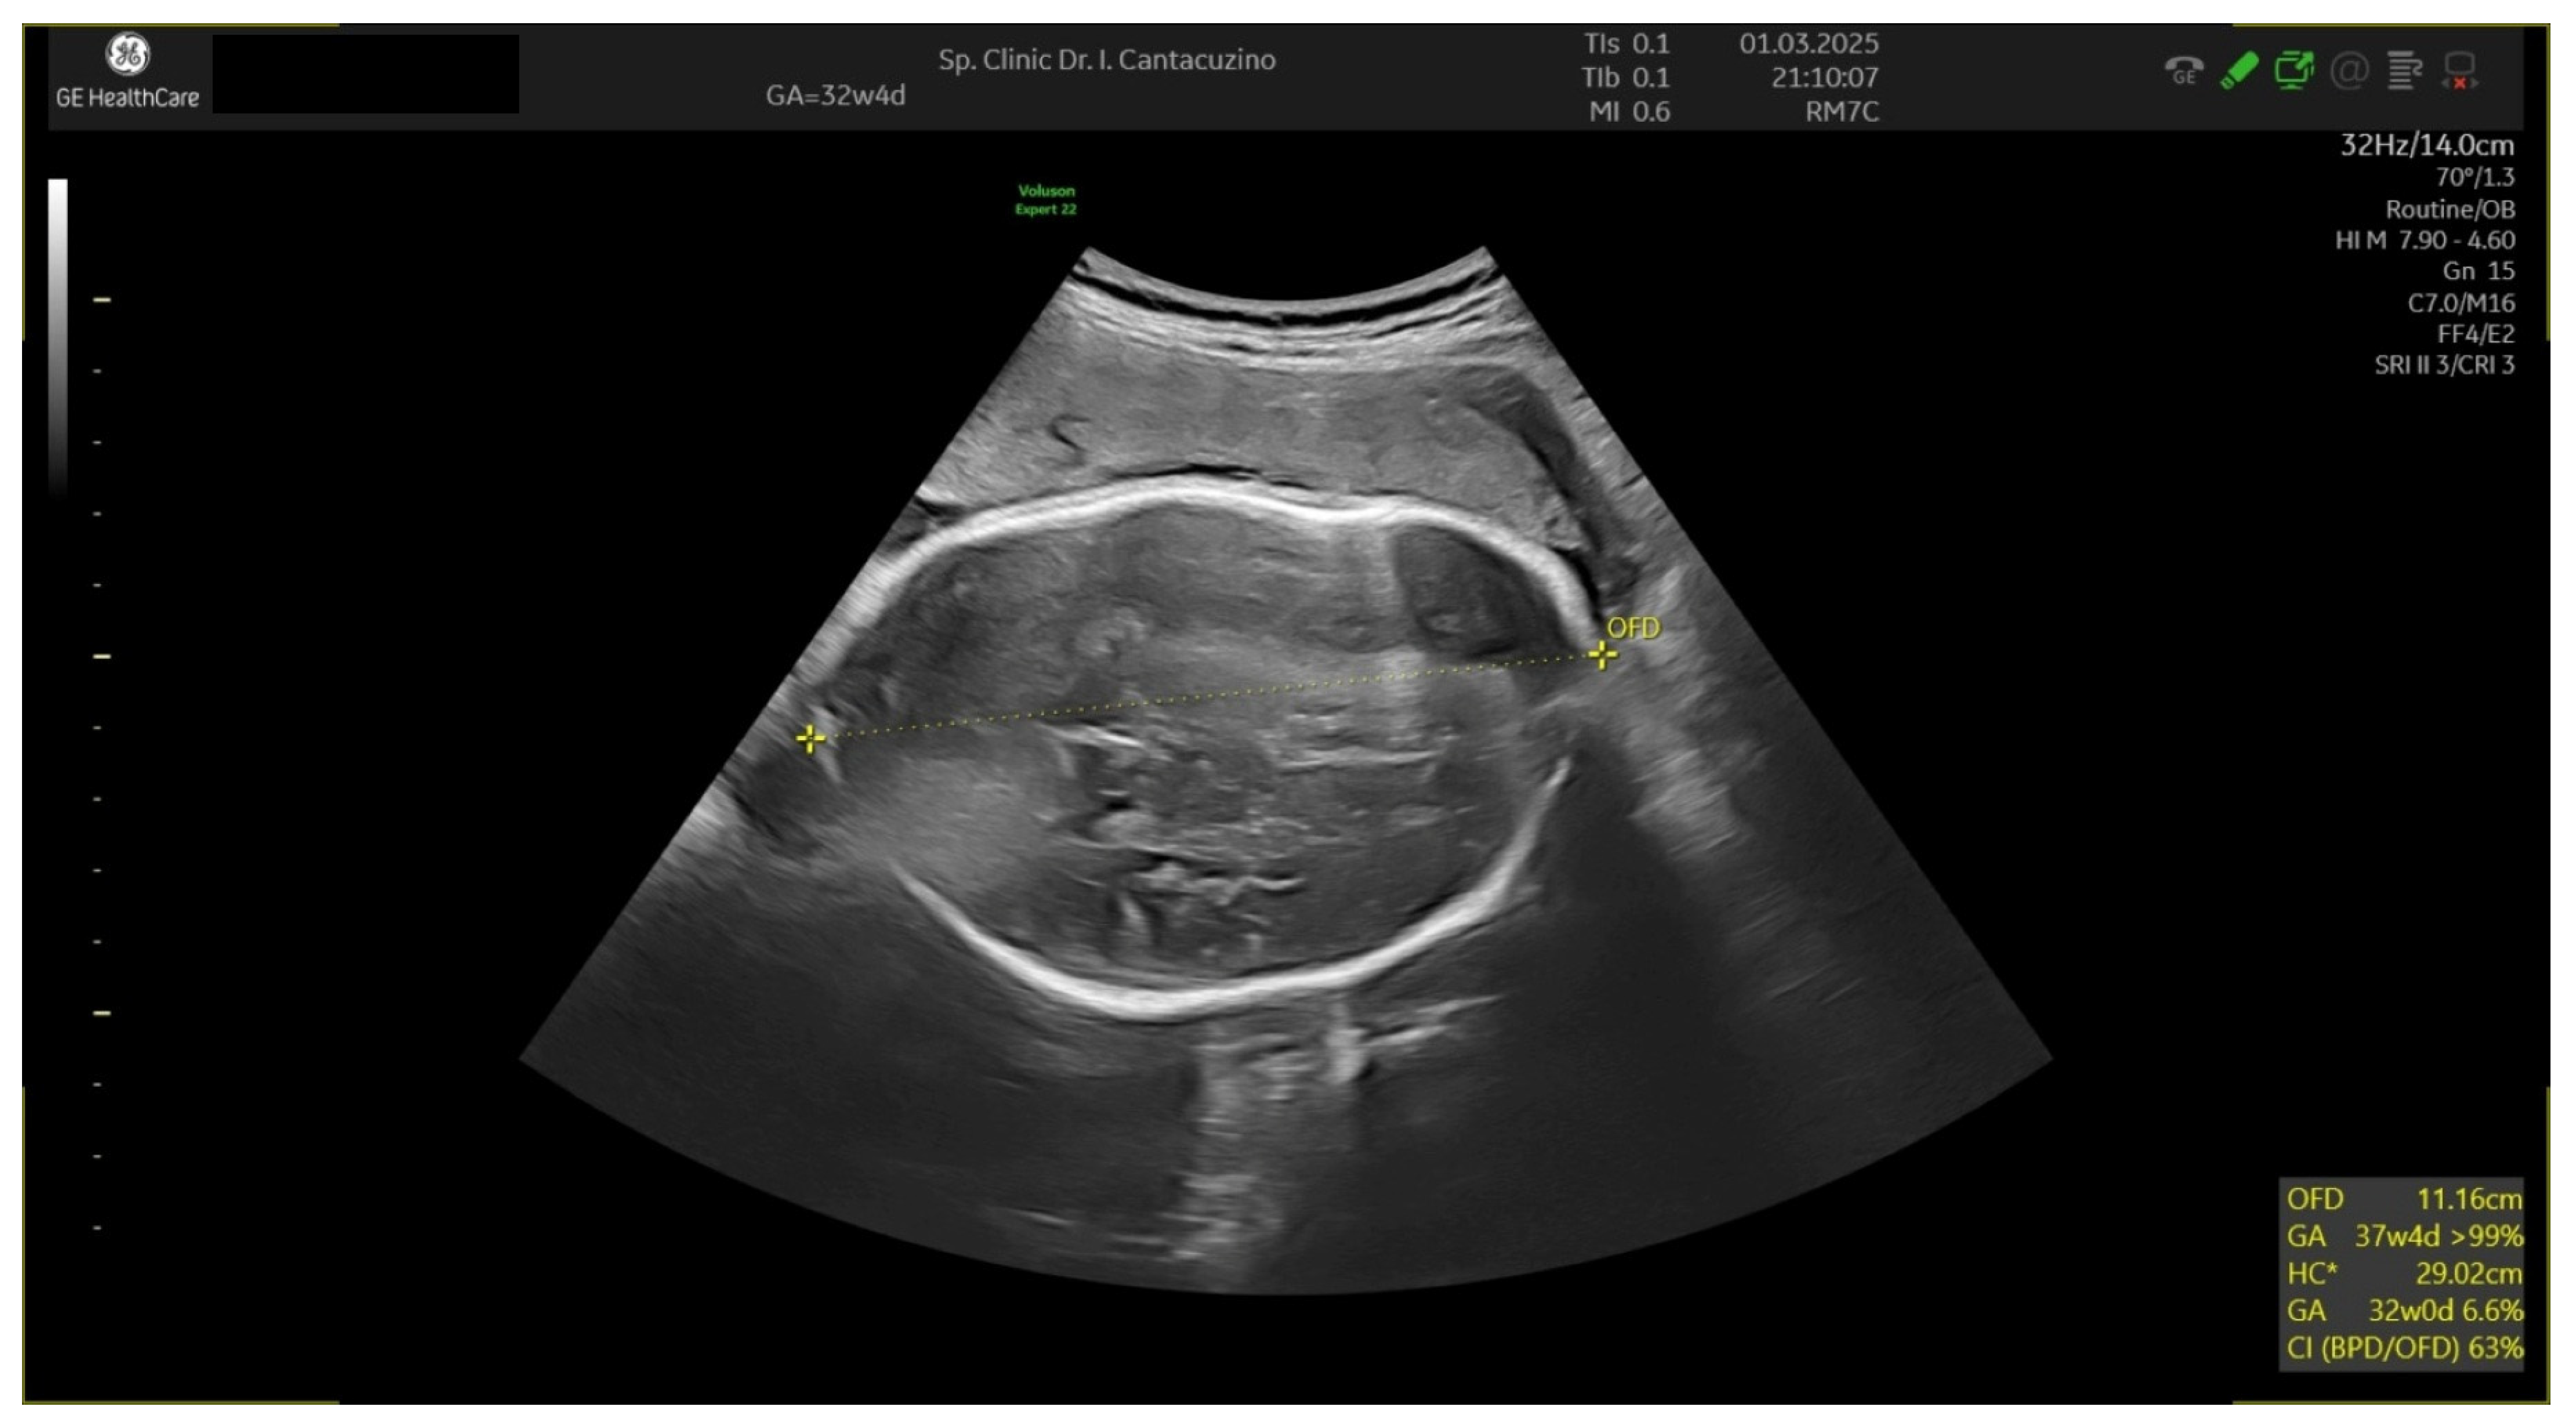

3.2. Patient Number 2

| Gestational Age (Weeks) | 27 Weeks | 29 Weeks | 32 Weeks 2 Days | 32 Weeks 4 Days |

|---|---|---|---|---|

| EGF | 967 | 1186 | 1548 | 1560 |

| Hadlock % | 15 | 12 | 4.1 | 3.1 |

| BPD | 5.96 | 6.43 | 6.76 | 7.08 |

| HC | 25.49 | 26.8 | 28.7 | 29.35 |

| AC | 22.2 | 23.83 | 25.94 | 25.95 |

| FL | 4.99 | 5.37 | 5.97 | 5.87 |

| AFI modified | no | no | no | no |

| Barcelona index | no | no | Barcelona stage I | Barcelona stage I |

| IVS thickness (mm) | 1.91 | 2.14 | 4.03 | 4 |